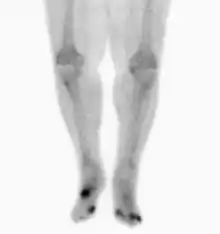

Nuclear medicine scans can be a helpful adjunct to MRI in patients who have metallic hardware that limits or prevents effective magnetic resonance. Generally a triple phase technetium 99 based scan will show increased uptake on all three phases. Gallium scans are 100% sensitive for osteomyelitis but not specific, and may be helpful in patients with metallic prostheses. Combined WBC imaging with marrow studies has 90% accuracy in diagnosing osteomyelitis.[25]